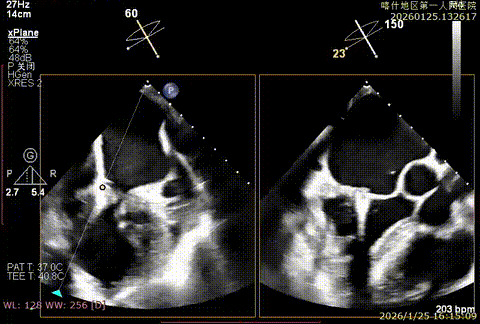

该例患者为DMR类Barlows患者,二尖瓣重度反流,患者1,2,3区均可见脱垂,脱垂主要源于3区,反流主要源于3区。术前制定手术策略:使用一把XTR解决患者瓣叶脱垂与二尖瓣反流。术中进行房间隔穿刺后将XTR-CDS送入左心房,通过操控“M”旋钮,成功将二尖瓣夹定位于2区正上方。在2区进行弹道测试成功后,进行Orientation调整。在3区将二尖瓣夹送入左心室,成功捕捞和夹持瓣叶后缓慢关紧夹臂,解决大部分反流,Saide by Saide L植入第二把XTR。TEE检查见二尖瓣反流程度充分降低至1+,二尖瓣双孔组织桥稳定,跨瓣压差3mmHg,肺静脉逆流改善明显,手术安全结束。

X-plan切面3区后叶脱垂

X-plan切面重度反流

XTR初定位

XTR终定位

成功捕捞并夹持

组织桥稳定